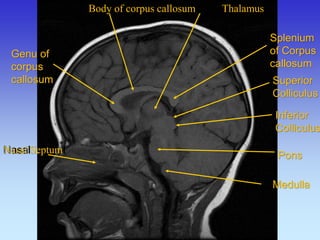

Body of corpus callosum Thalamus

Splenium of Corpus callosum

Genu of corpus callosum

Pons

Superior Colliculus

Inferior

Colliculus

Nasal

Septuml

Medulla